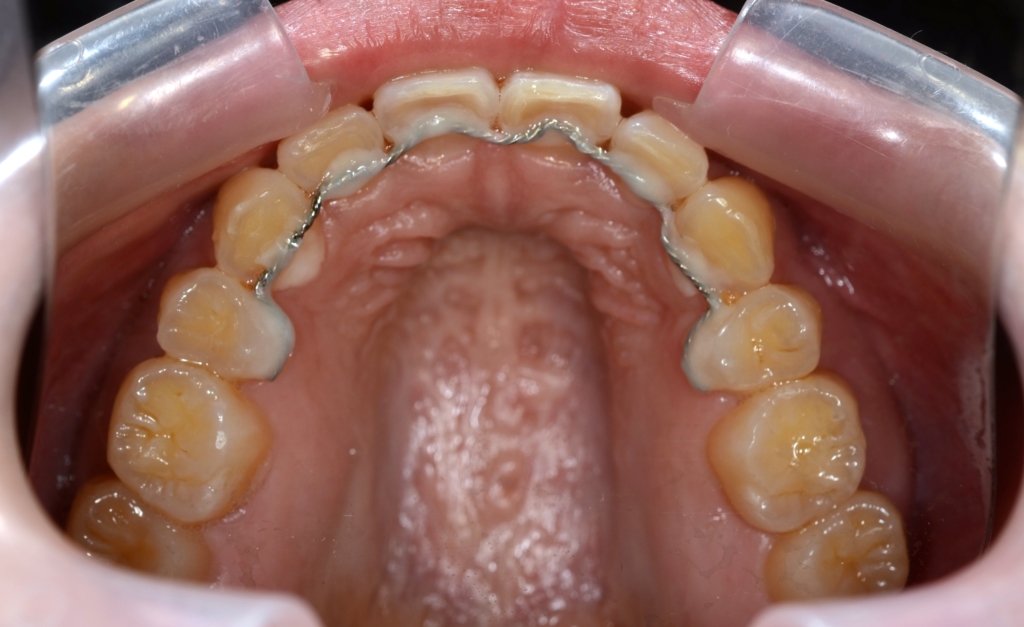

【保定】 上下ともフィックスタイプ&クリアリテーナー

【治療期間】 3年2カ月間

【治療費用】 87万6千円

【治療装置】 ハーフホワイトtypeのマルチブラケットシステム、

アンカースクリューを計4本

PLAS & パラタルバー

口蓋のアンカースクリューにPLAS&パラタルバーをセットして、上の歯列全体を後方へ移動させます。

先ずは、その準備として上顎の口蓋にアンカースクリューを追加で植立します。

そこで、上の歯列全体をより後方へ移動させることで、より引っ込んでいる下の歯列に合わせることで、口元も引っ込めることにしました。